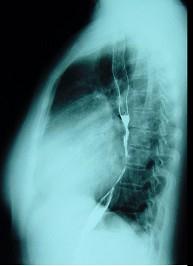

对如下心脏左侧位片描述正确的是 ( )A、正常心脏B、以上均错C、左心房Ⅱ度增大D、右心室增大E、右心房增大

选项 A、正常心脏 B、以上均错 C、左心房Ⅱ度增大 D、右心室增大 E、右心房增大

答案 C